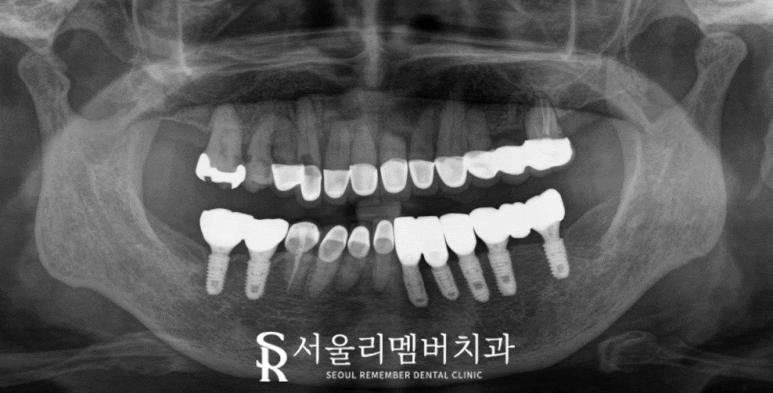

파노라마를 살펴보면

말씀하신 대로

하악 전치 부근

치근 끝으로 염증이 생겨있습니다.

아마도 기존 크라운 내부로

이차 충치가 생기면서

그 틈으로 충치균이 들어가

치수가 감염된 것 같네요.

감염된 치수의 염증이

빠져나갈 곳이 없으니

뿌리 끝에 농양을 만들었을

가능성이 높습니다.